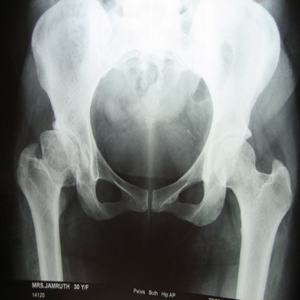

Arthriis of both hips pre op Arthriis of both hips post op Arthritis knee valgus deformity pre op Arthritis knee valgus deformity post op